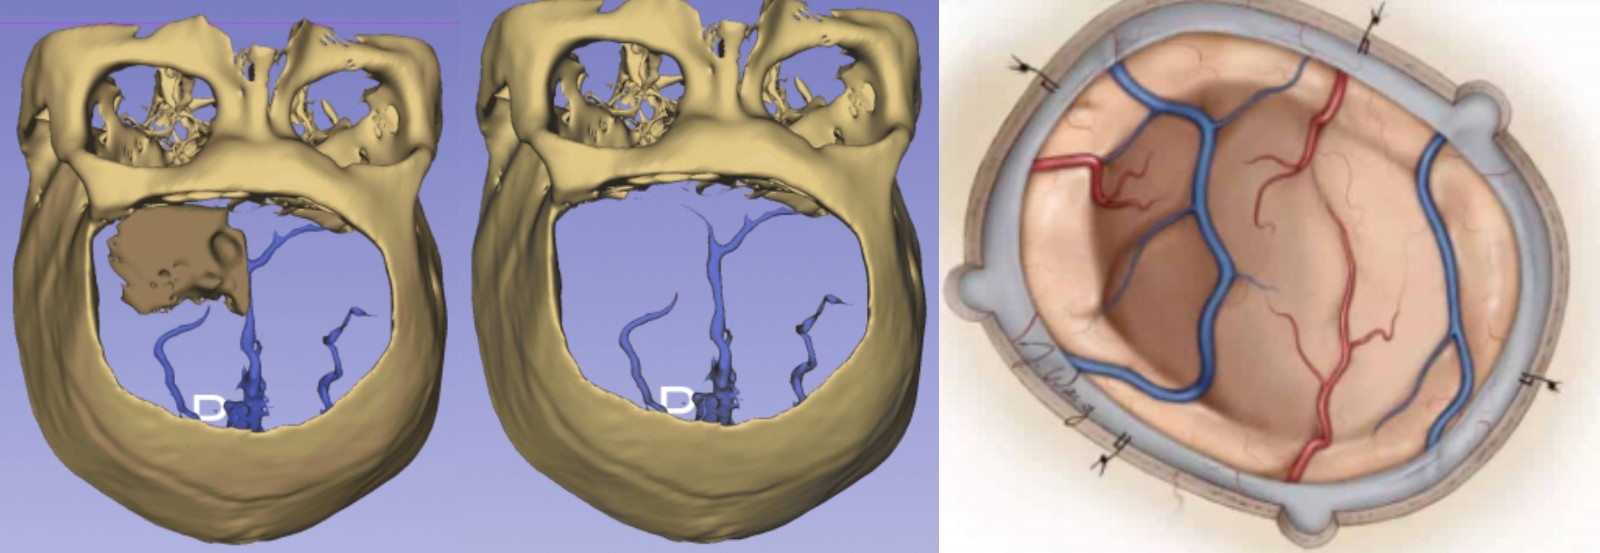

腫瘤與靜脈、矢狀竇的關系

靜脈影像重建

■ 使用“導板”確定骨窗范圍,用記號筆標記。中線及兩側鉆孔4枚,沿標記內側2mm銑下骨瓣,暴露矢狀竇,注意矢狀竇旁蛛網膜顆粒出血,明膠海綿壓迫,必要時時抬高背板;

■ 先行瘤內部分減壓,然后沿中線探查腫瘤與矢狀竇關系,進一步切斷腫瘤血供

■ 瘤體縮小后,沿腫瘤與腦組織/血管蛛網膜界面分離,逐漸分塊切除腫瘤

■ 過程中保護周圍正常腦組織及正常皮層引流靜脈

■ 修整骨窗邊緣,額竇開放使用骨蠟+骨膜封閉(骨膜受累時取腹部脂肪填塞)

■ PEEK材料放置妥帖,懸吊硬腦膜,顳肌吊至PEEK材料上,留置皮下引流管